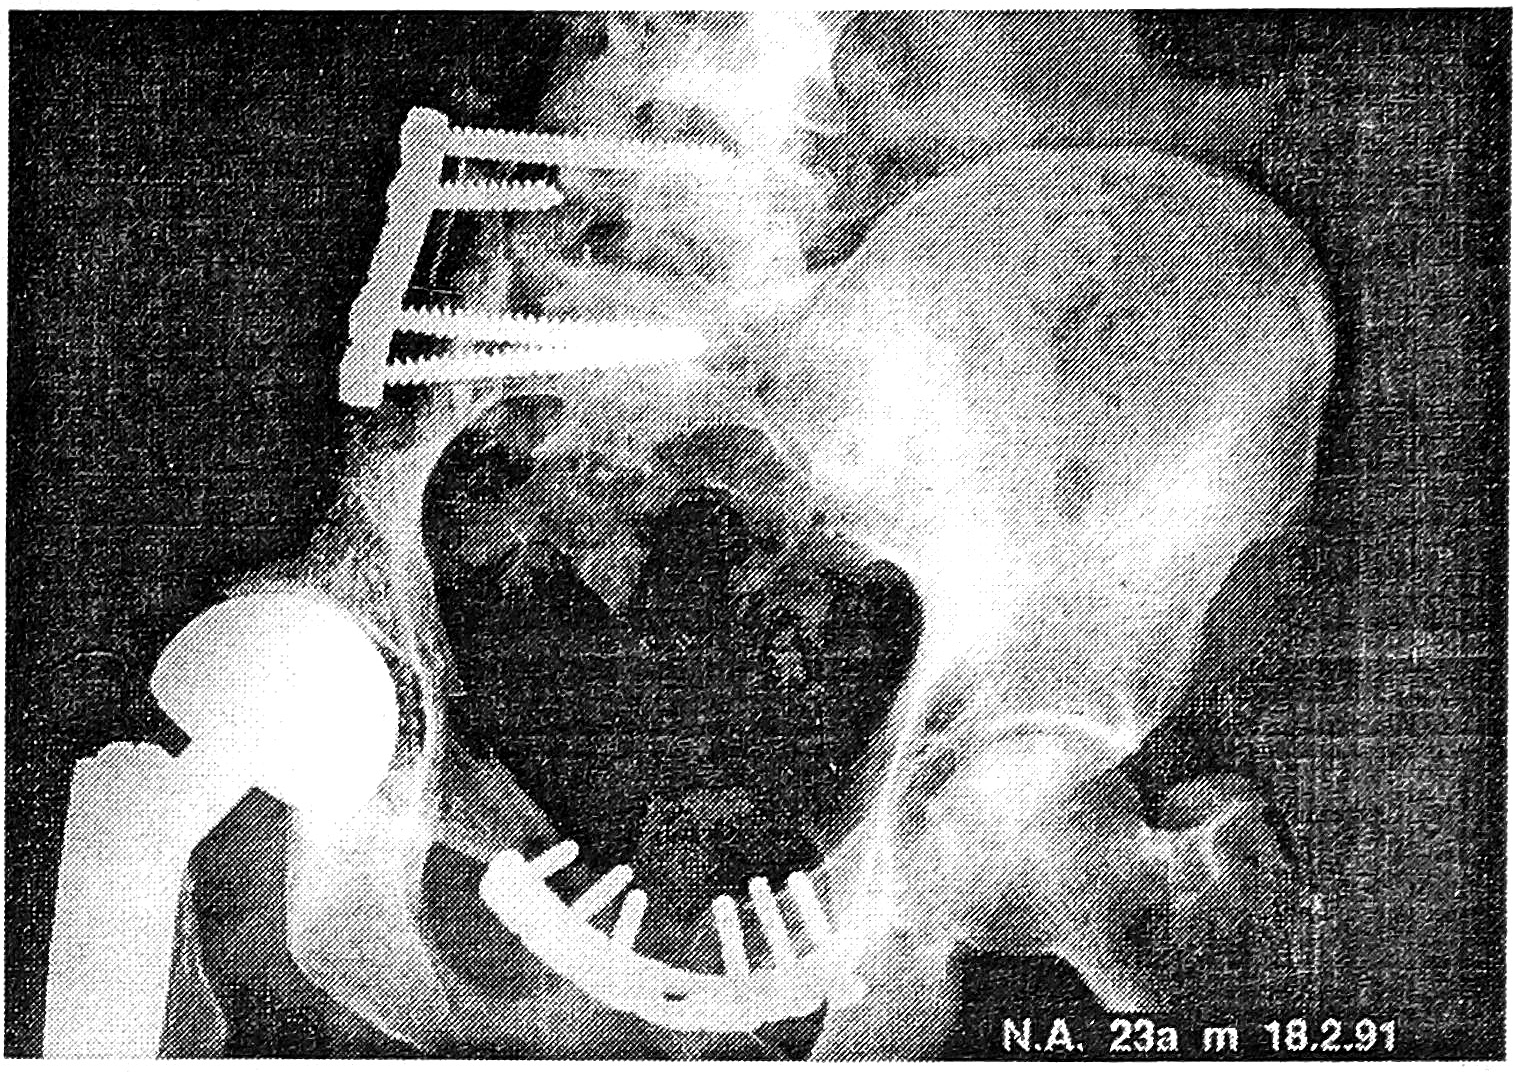

Рис. 2. Рентгенограмма больного 23 лет после резекции правой половины таза по поводу саркомы Юинга с замещением дефекта аллотрансплантатом в сочетании с эндопротезированием тазобедренного сустава однополюсным протезом. Неудача операции из- за развития инфекции спустя 4 мес.